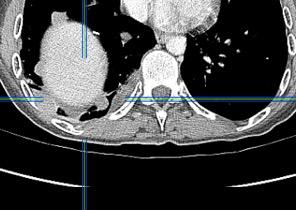

Signos radiológicos TC

Hallifax RJ et al. State-of-the-art: Radiological investigation of pleural disease Respiratory Medicine 2017

Nivel hidroaéreo o burbujas

Forma lenticular o elíptica Ángulos obtusos

> Grasa Extrapleural (60-80%)

Situación no gravitacional (no siempre)

Compresión de estructuras pulmonares

Límite muy bien definido Tabicación

Signo de la Pleura separada “Split pleural sign”

Capas pleurales de grosor uniforme realzadas por el contraste

No específico de empiema. Indica “exudado”. 68% de pacientes con empiema pleural.

Capas pleurales de grosor uniforme

Realce grasa extrapleural (30%)

> Grasa Extrapleural. (60-80%)

Kraus GJ. Split pleural sign. Radiology 2007